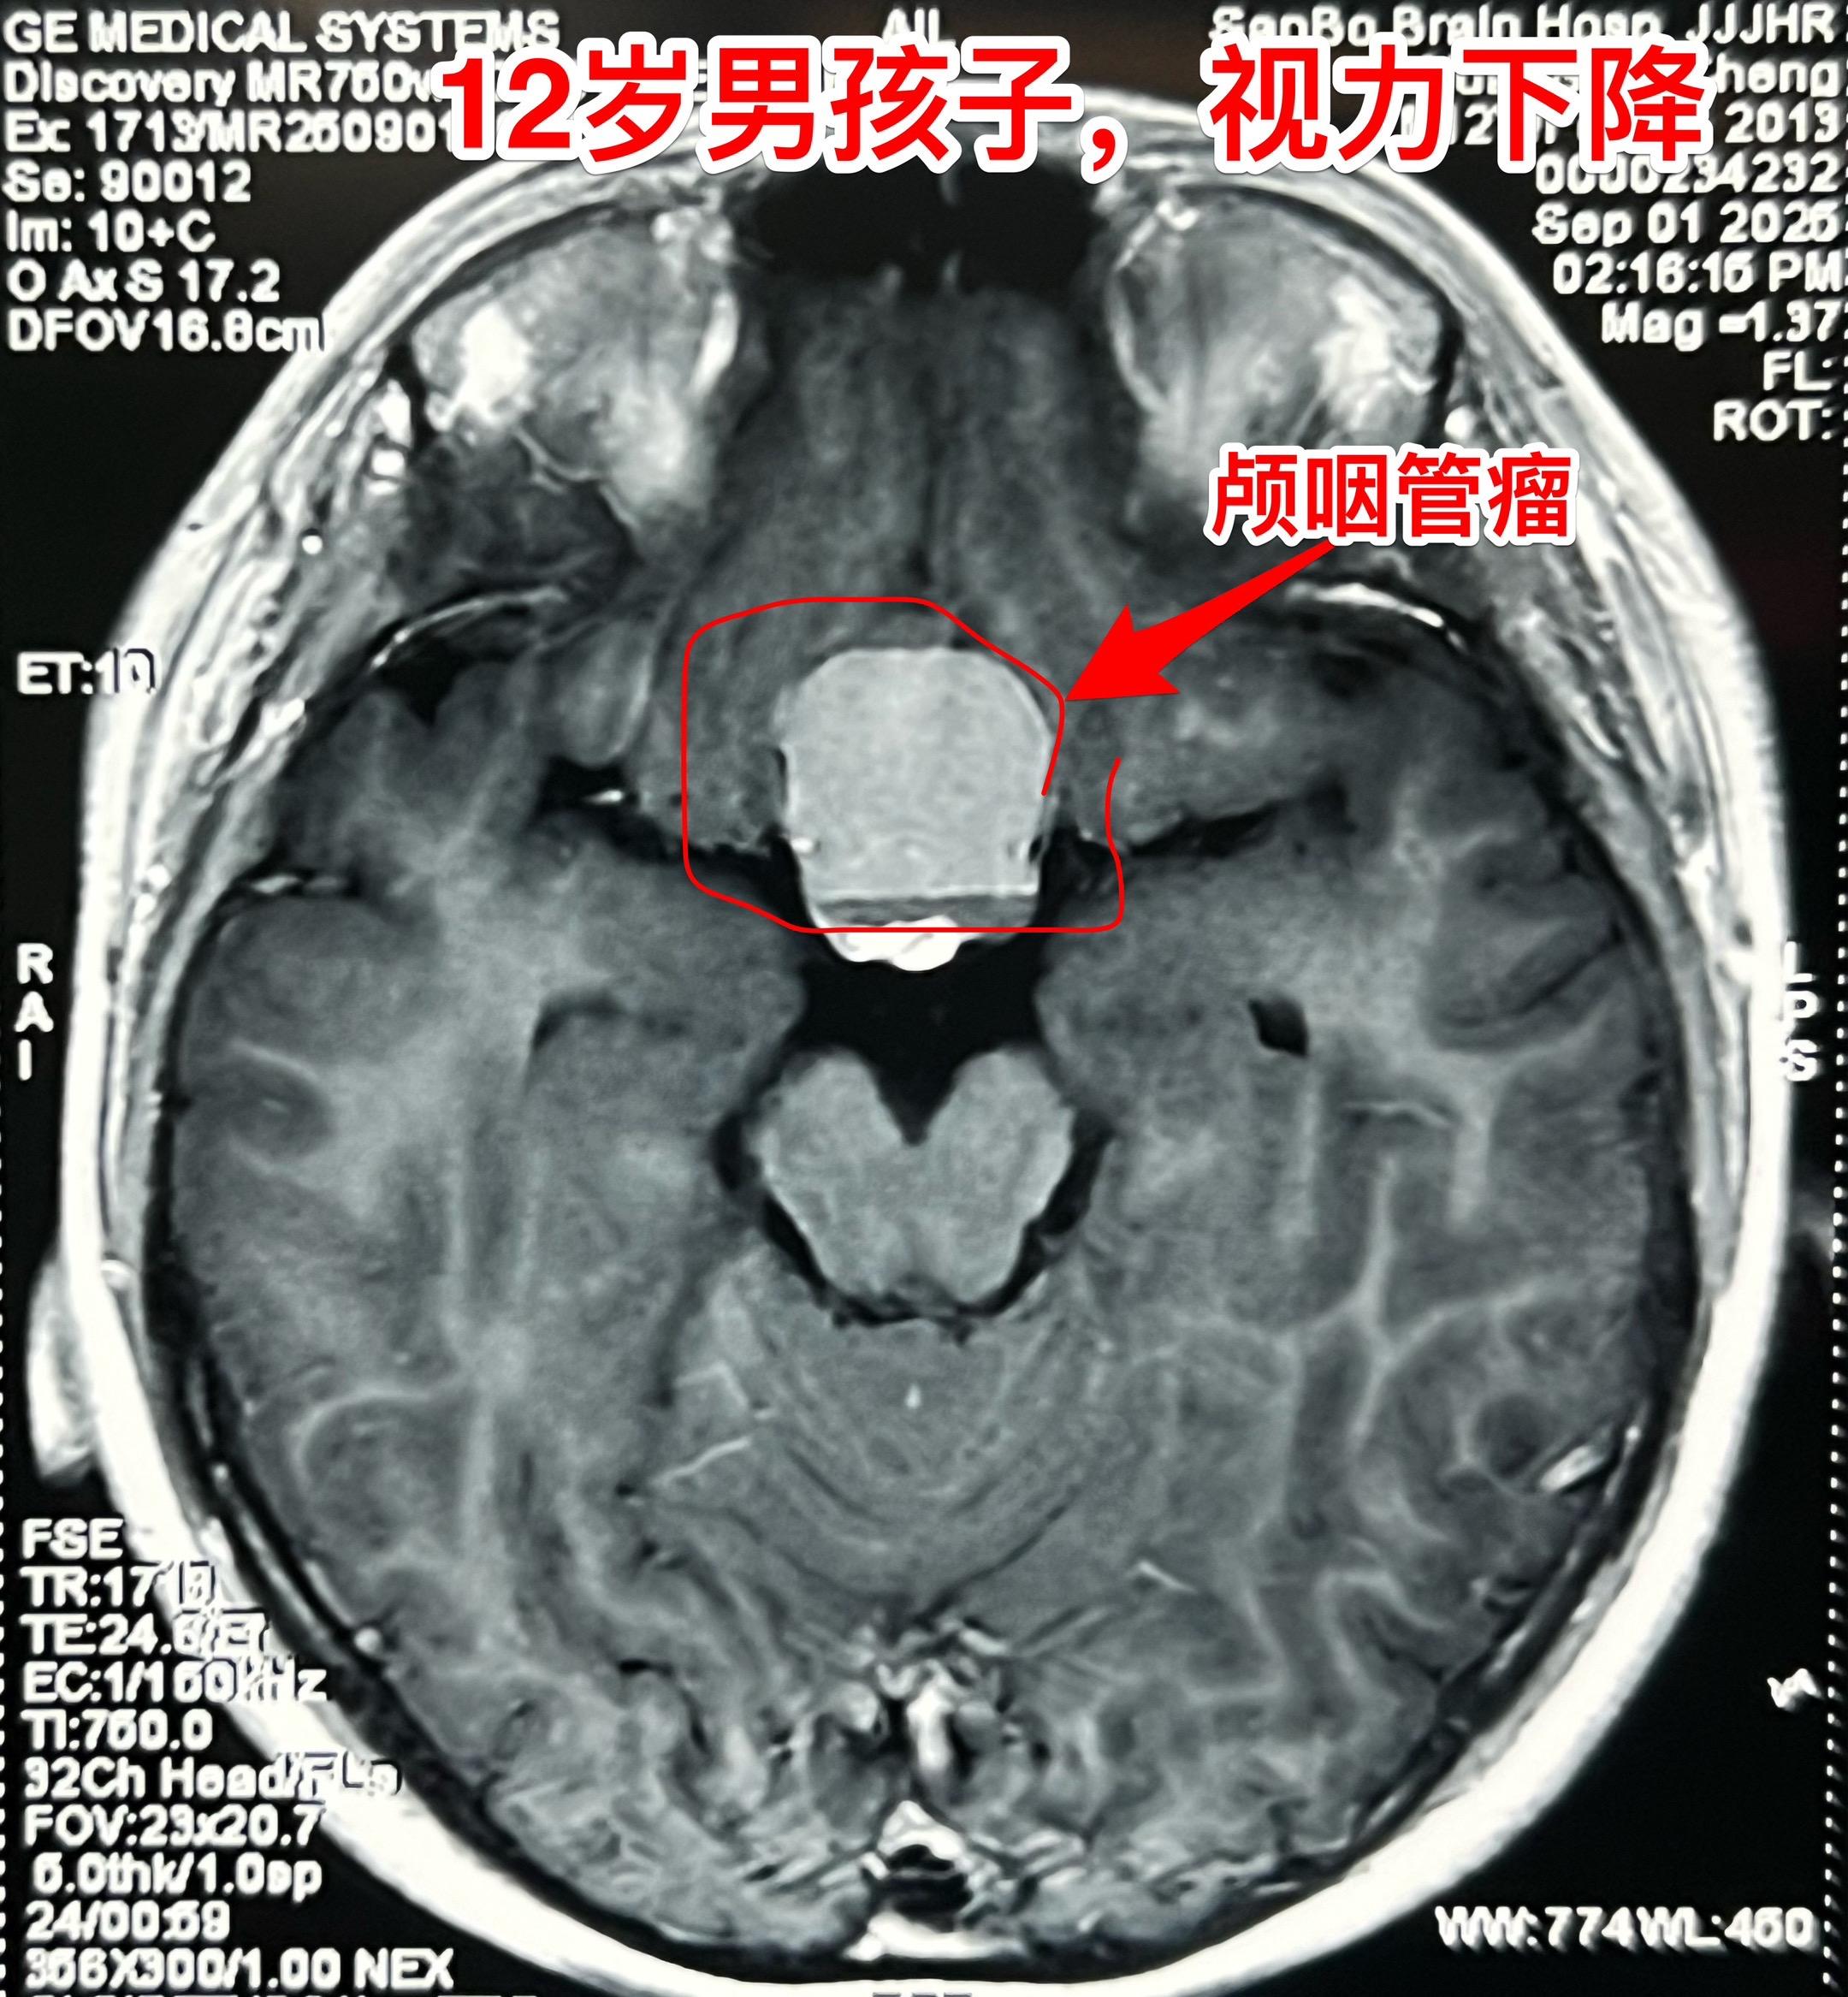

常规一天两个颅咽管瘤手术。今日两个颅咽管瘤手术。 上午第一个是12岁男孩子,江西人。八月份因视力下降到当地医院检查发现颅咽管瘤。八月底找我看病时双眼已经没有有效视力了。 磁共振和CT见图。图2标注:垂体和垂体柄结构清晰,提示在切除肿瘤时垂体和垂体柄很有希望得到保留。 肿瘤切除后垂体柄和垂体保护完好。可以预见男孩子的垂体功能应该会很好👍